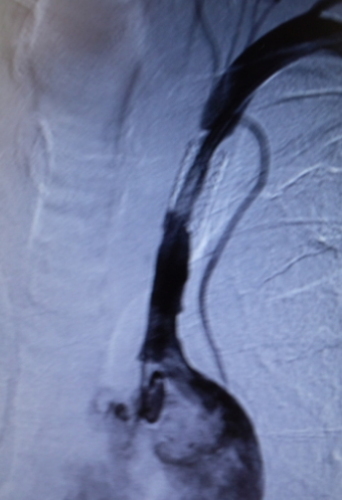

7月30日(月)に入院し、昨日7月31日(火)に手術して今日8月1日(水)に退院してきました。 左右の腕の最高血圧の差が30以上あったので動脈硬化症を疑って地元の総合病院へ行ったのが7月17日(火)だった。案の定、昨年末左鎖骨下閉塞性動脈硬化症の治療を行いステントを留置した部分の内部が再び閉塞していた。再閉塞したステントの部分befor 予定では、閉塞したステント内部にカテーテルを通しバルーンで拡張する治療法が短時間で行われる予定だったが手術中に色んなわけのわからない専門用語の会話が飛び交っていたが、留置してあるステントより長い(倍くらい)のステントをステント内に挿入し、留置する方法がとられ、手術に要した時間はおおむね一時間半かかってしまった。after 詰まっていたステントの内側とその延長部分が綺麗になったがこれで自分の体内(動脈)には3本のステントが留置された。